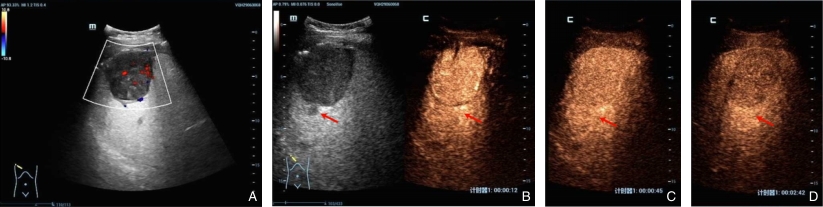

图3 超声影像 A:常规超声示,肝右前叶低回声肿块及结节,内可见点条状血流信号;B-D:超声造影示,较大肿块于动脉期呈高增强,内可见杂乱血管影,门脉期及延迟期呈低增强,周边所见结节(箭头所示)对应动脉期呈高增强,门脉期及延迟期呈等增强Fig.3 Ultrasound findings A: Conventional ultrasound shows a hypoechoic mass and nodules in the right anterior lobe of the liver, with punctate and linear blood flow signals within; B-D: Contrast-enhanced ultrasound shows marked hyperenhancement of the larger lesion in the arterial phase with disorganized intralesional vessels, followed by hypoenhancement in the portal and delayed phases, and the peripheral nodules (as arrows indicated) show hyperenhancement in the arterial phase and isoenhancement in the portal and delayed phases